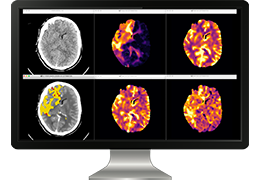

ART-Plan™ Artificial Intelligence Contouring